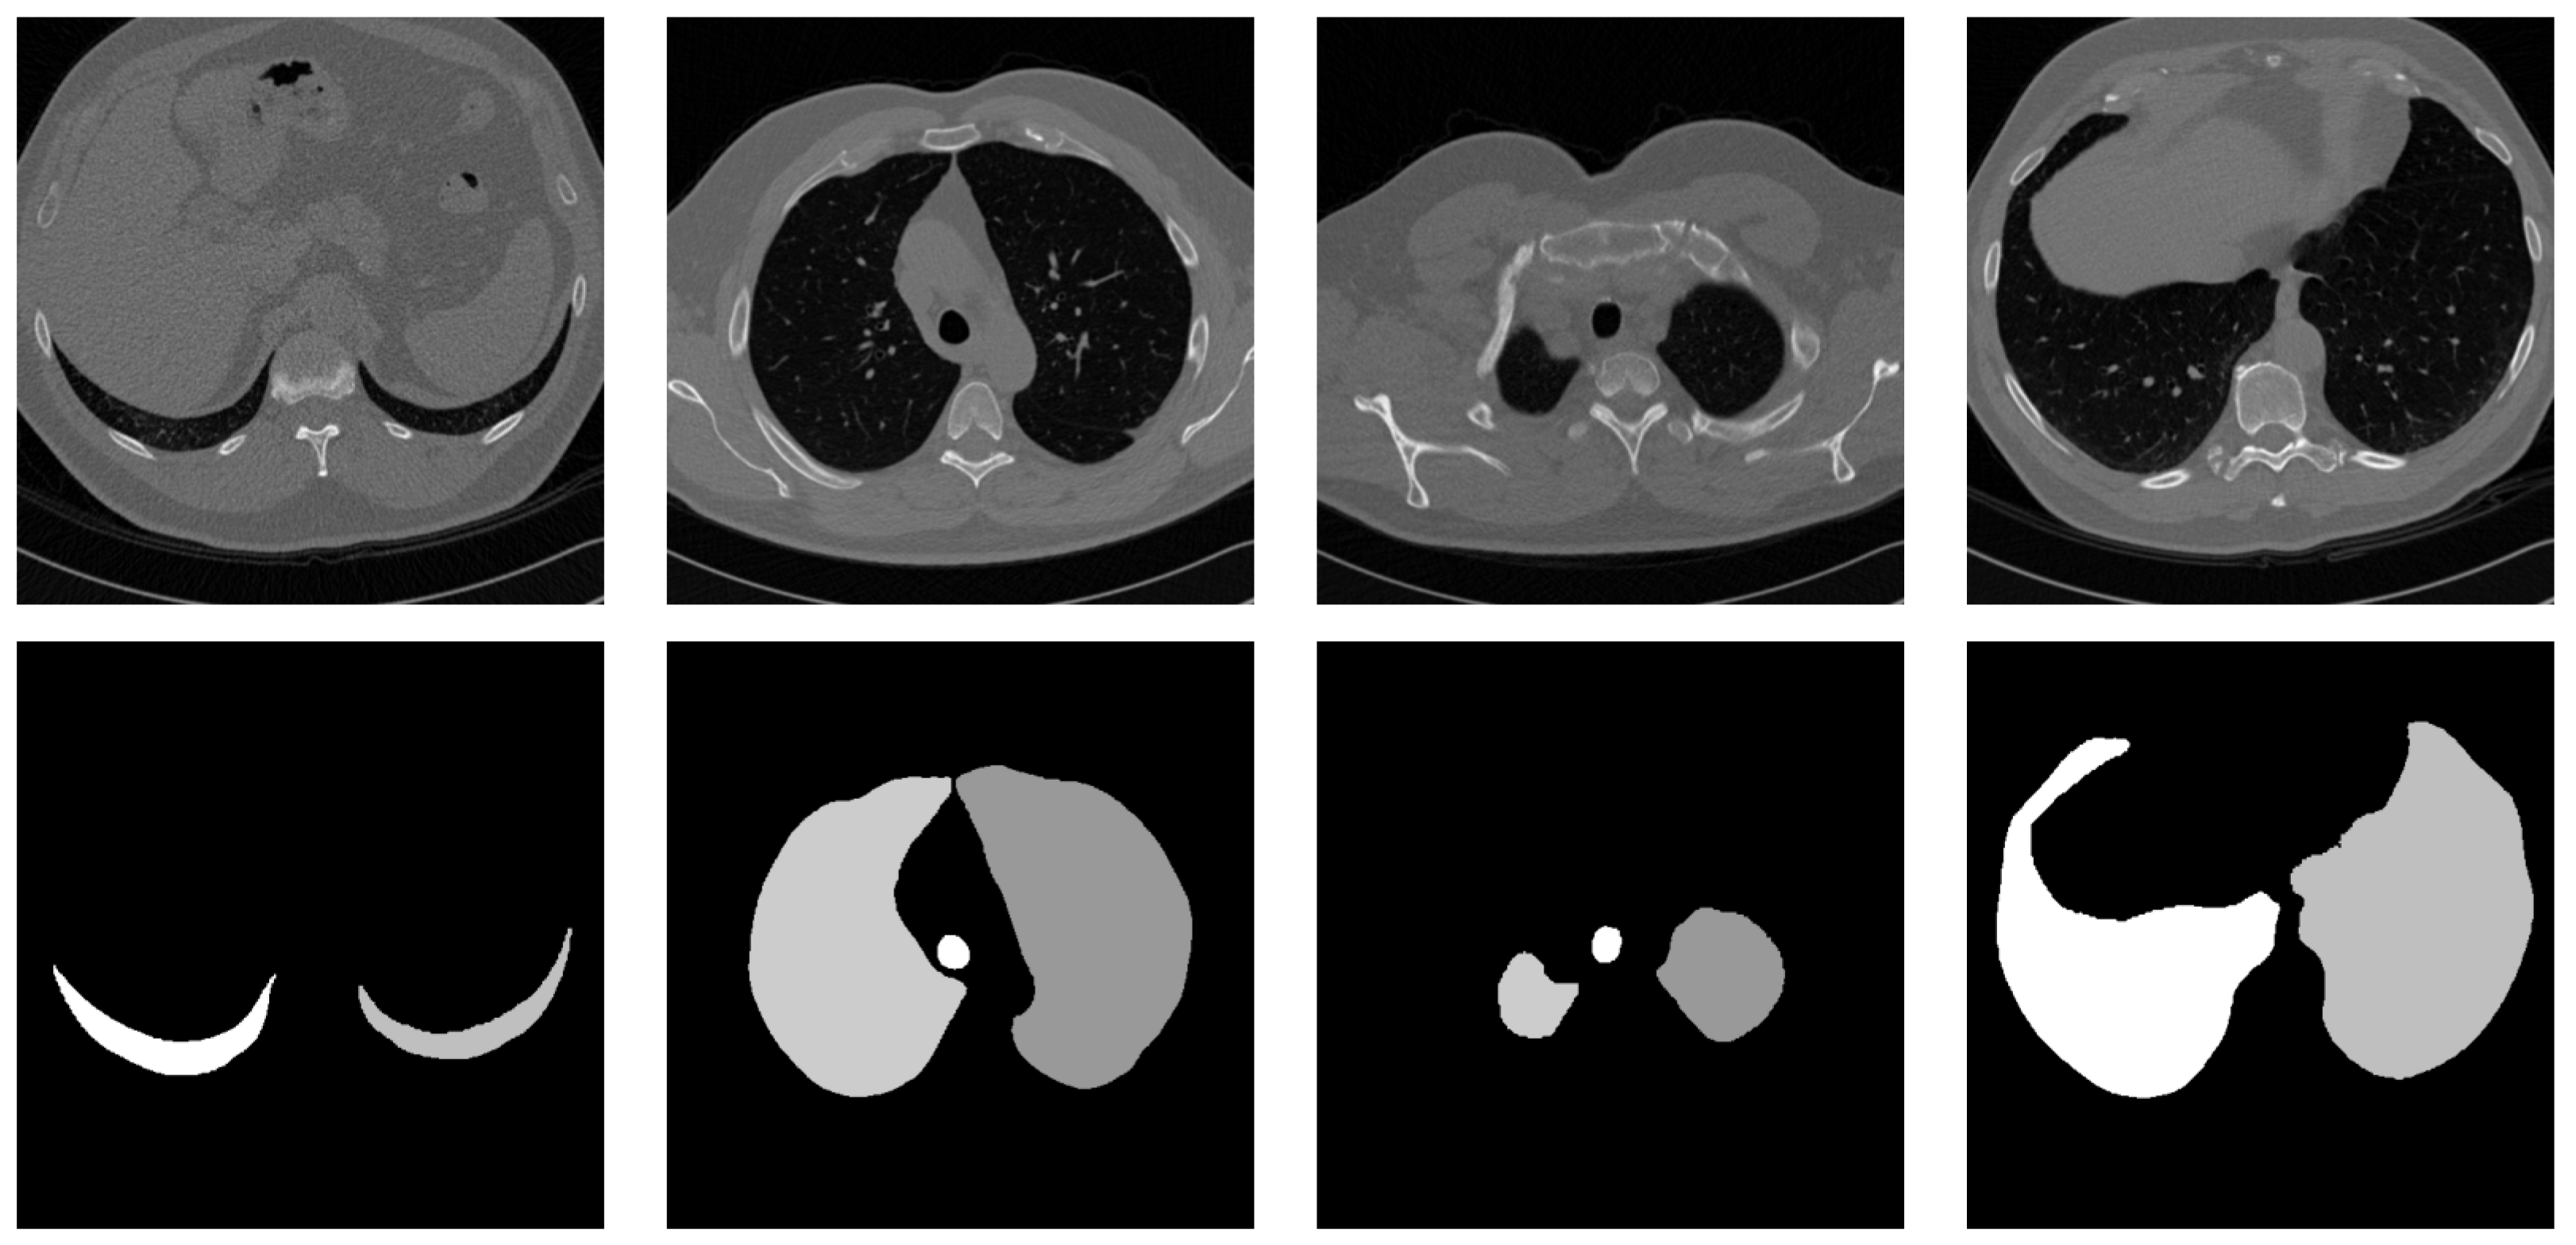

4.2. Qualitative Results